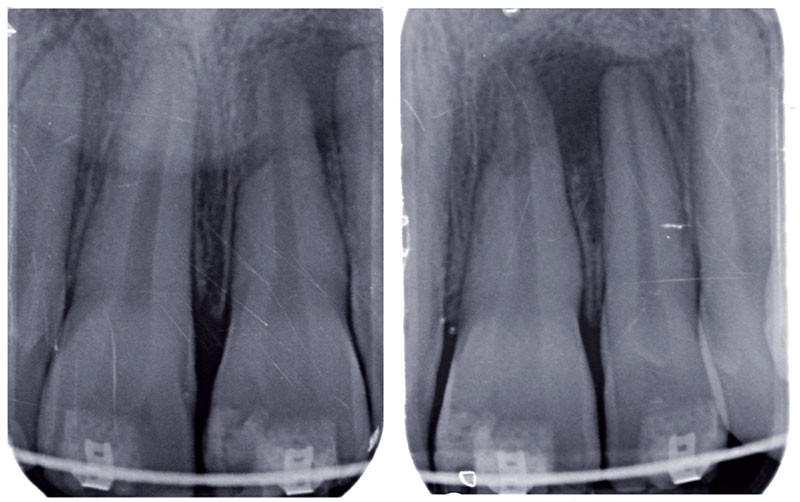

La cicatrisation des lésions inflammatoires péri-radiculaires d’origine endodontique (LIPOE) est un enjeu de la pratique quotidienne de la dentisterie. La prévalence de cette maladie est très élevée dans le monde. Les patients, les praticiens et la société dans laquelle chacun évolue, sont concernés par l’évidente difficulté à l’éradiquer. Aujourd’hui, les limites de conservation de la pulpe sont nettement repoussées, et c’est une façon de procéder à la prévention de l’apparition des lésions apicales. Demain, cette approche biologique va s’ouvrir sur la zone apicale et la prise en charge du traitement des lésions d’origine endodontique se fera sur la base des connaissances biologiques des processus de guérison. Pour l’heure, il est possible d’investir la question sous cet angle, de reprendre les critères cliniques et radiologiques de guérison apicale et de mettre en valeur, par la pertinence des techniques choisies, la notion d’efficacité dans la guérison.

Le traitement d’une lésion apicale d’origine endodontique dépend de la mise en œuvre efficace des techniques de traitement par voie orthograde ou par voie chirurgicale; par le choix éclairé de la méthode utilisée, il est possible d’améliorer la cinétique de guérison.

En 2002, une étude française a montré que plus de 66 % des patients étaient porteurs d’au moins une lésion apicale [1]. Si l’on considère que les méthodes d’analyse et d’observation se fondaient sur la base d’examens radiographiques en deux dimensions, on mesure à l’heure du Cone Beam Computerized Tomography (CBCT) que ces chiffres seront revus à la hausse [2].